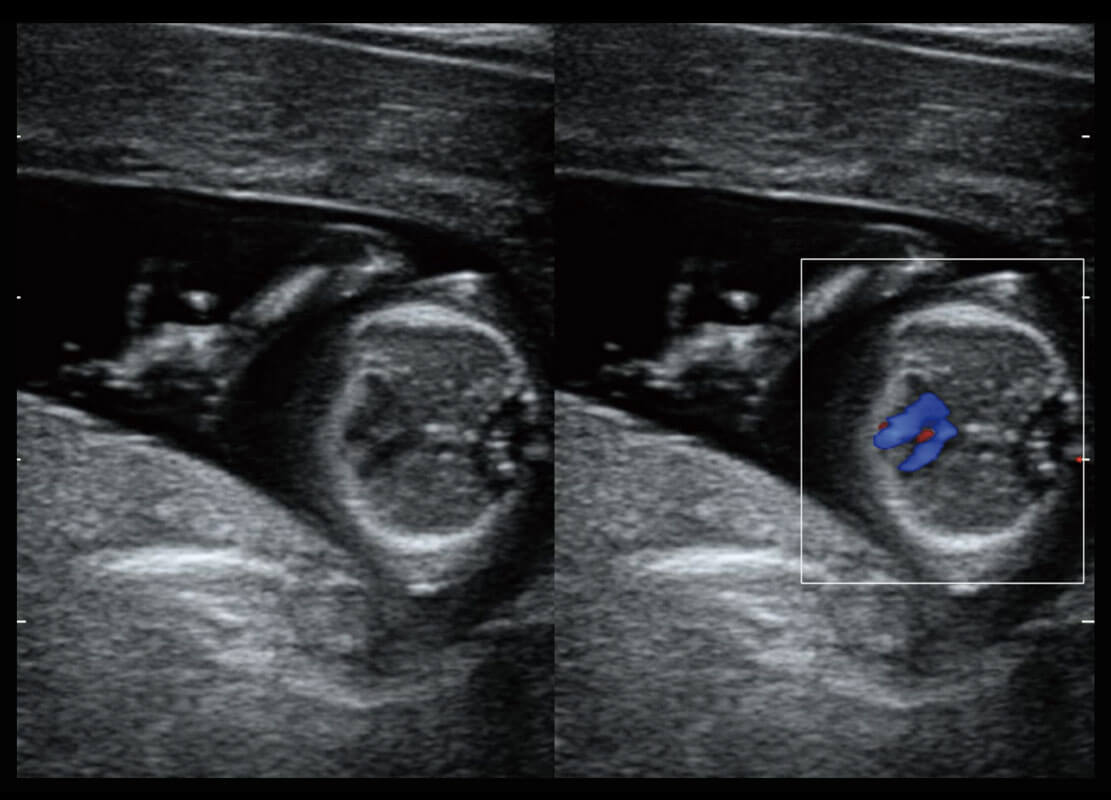

早孕-胎心

高分辨率容积成像-早孕胎儿

胎儿体循环

光影成像-孕囊